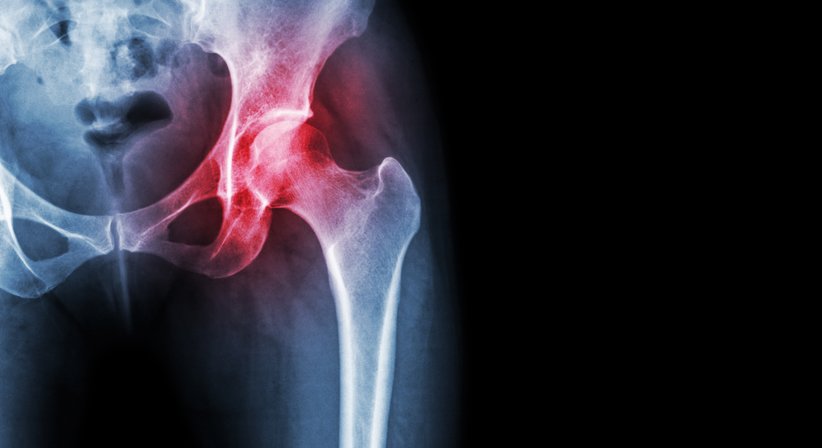

Beim Hüft-Impingement handelt es sich um ein Engpass-Syndrom der Hüfte, das mit stechenden, dumpfen Schmerzen im Leistenbereich, Bewegungseinschränkungen und Überlastungen des Gelenks einhergeht. Ohne Therapie steigt das Risiko für eine frühzeitige Entwicklung einer Hüftarthrose.